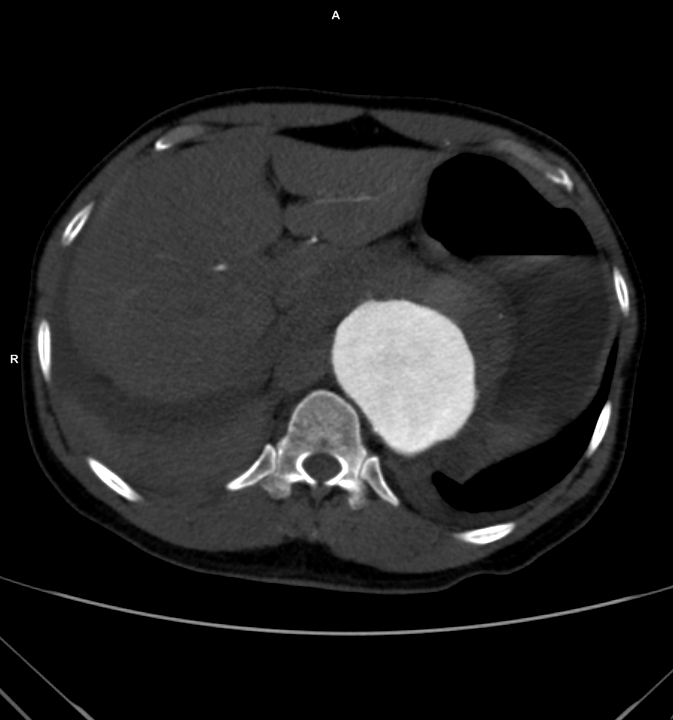

The patient is a woman in her 60’s who self referred for complaint of abdominal pain, weight loss, and rest pain of the lower extremities. She is a 40 pack year smoker and had severe COPD, hypertension, congestive heart failure with mitral regurgitation, chronic kidney disease stage IV, and ischemic rest pain of the legs. She had a 30 pound weight loss due to severe postprandial abdominal pain. She had bloody stools. Her kidney function was worsening, and dialysis was being planned for likely renal failure but she was against dialysis. She had consulted several regional centers but was felt to be too high risk for surgery and with her refusal of dialysis, would be a high risk for renal failure and death with intervention. Physical examination revealed weakened upper extremity pulses, and nonpalpable lower extremity pulses and a tender abdomen. In clinic, she developed hypoxia and dyspnea and was admitted directly to the ICU.

CTA (above) revealed severely calcified atherosclerotic plaque of her visceral segment aorta occluding flow to her mesenteric and renal arteries and to her leg. The right kidney was atrophic. The left kidney had a prior stent which looked crushed. The infrarenal aorta was severely diseased but patent and there were patent aortic and bilateral iliac stents.